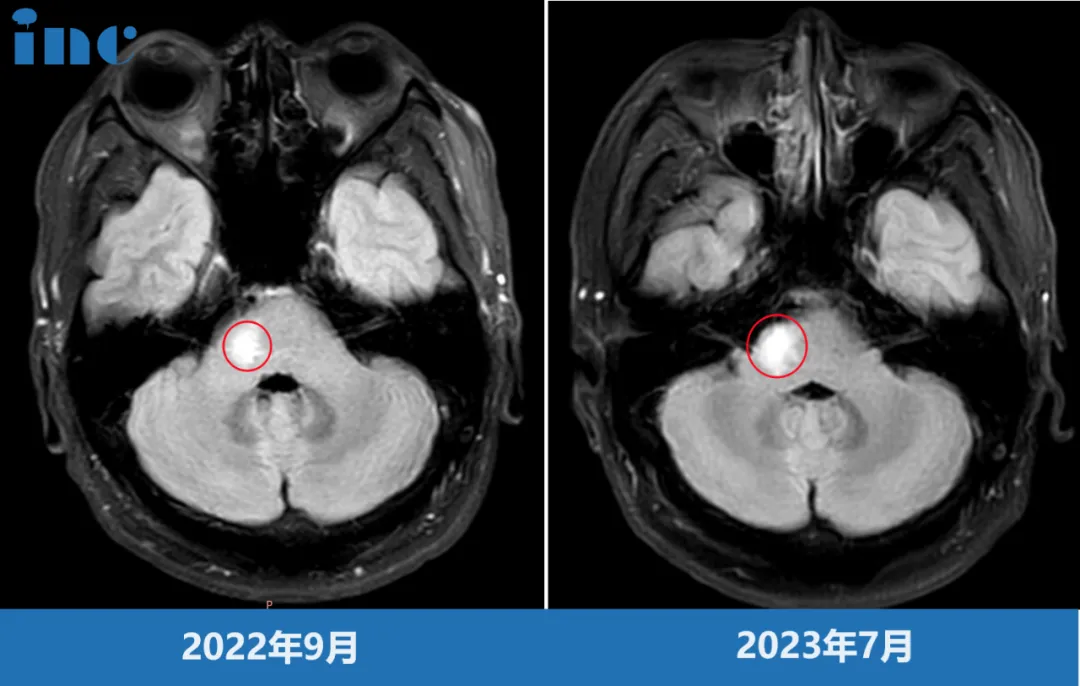

脑干-桥臂胶质瘤长大,三根重要神经包绕肿瘤

命运总会在人意气风发的时候,悄悄伸出脚把你绊倒。韩先生、30出头、高级工程师,正是家庭和事业蒸蒸日上的时候,这时却被胶质瘤病魔的触角缠住。短短不到一年,由初次诊断的疑似脱髓鞘病变,到病灶增大、怀疑胶质瘤。一边需要全身心投入高精尖工作之中,一边四处求医。“桥臂位置处于大脑深部,手术难度、风险都很大,不建议手术。”原本充满朝气的生活如今度日如年,心力憔悴的韩先生此时无路可走。

韩先生术前影像

脑干桥臂位置,肿瘤还被面神经,滑车神经,听神经等重要神经包绕,手术难度之大不言而喻。巴教授是他们希望。2023年9月29日,中秋节当天,巴教授为韩先生成功手术。